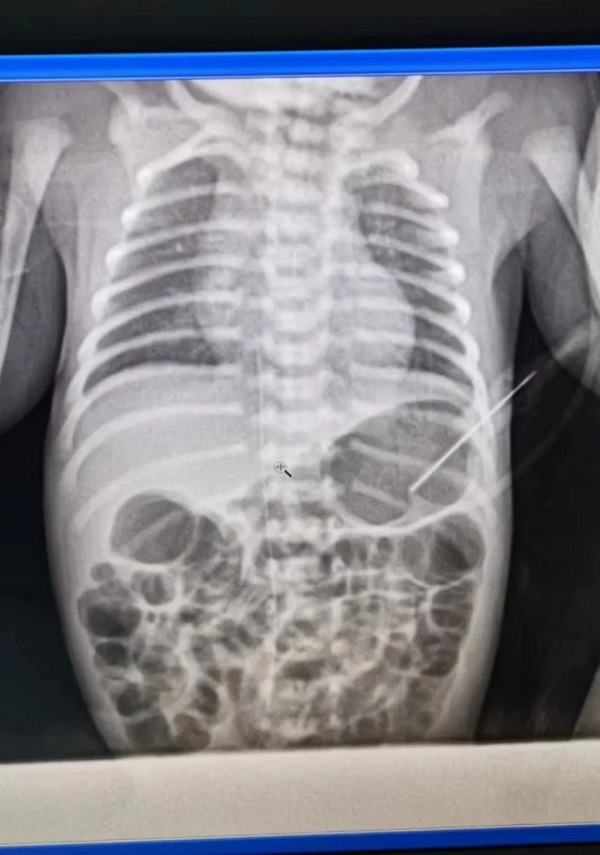

患儿皮肤娇嫩,血管细,穿刺过程十分严谨细致。新生儿科护士顺利地为患儿完成了在右下肢大隐静脉内经外周静脉置入中心静脉导管术(PICC),操作过程顺利,患儿术中生命体征平稳。

放射科X线定位,最终确定PICC管末端成功置入下腔静脉与右心房交界处。(为PICC置入的最佳位置)